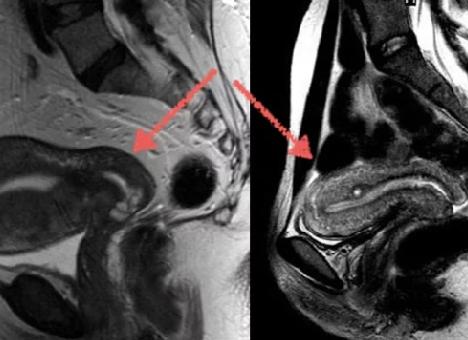

В ходе МР-исследования тазовой области происходит сканирование тела человека и преобразование полученных результатов в серию послойных снимков, каждый из которых представляет собой срез толщиной до 1мм. При необходимости полученные изображения впоследствии могут быть преобразованы в трехмерные модели органов.

Одним из основных преимуществ магнитно-резонансного исследования таза перед другими методами диагностики является возможность получать изображения сканируемых объектов в любой плоскости и необходимой крупности. Благодаря высокой разрешающей способности МРТ, на снимках можно различать объекты размером до нескольких миллиметров. Это позволяет наиболее полно оценить состояние тех или иных структур, что особенно важно при планировании оперативных вмешательств и лучевой терапии.